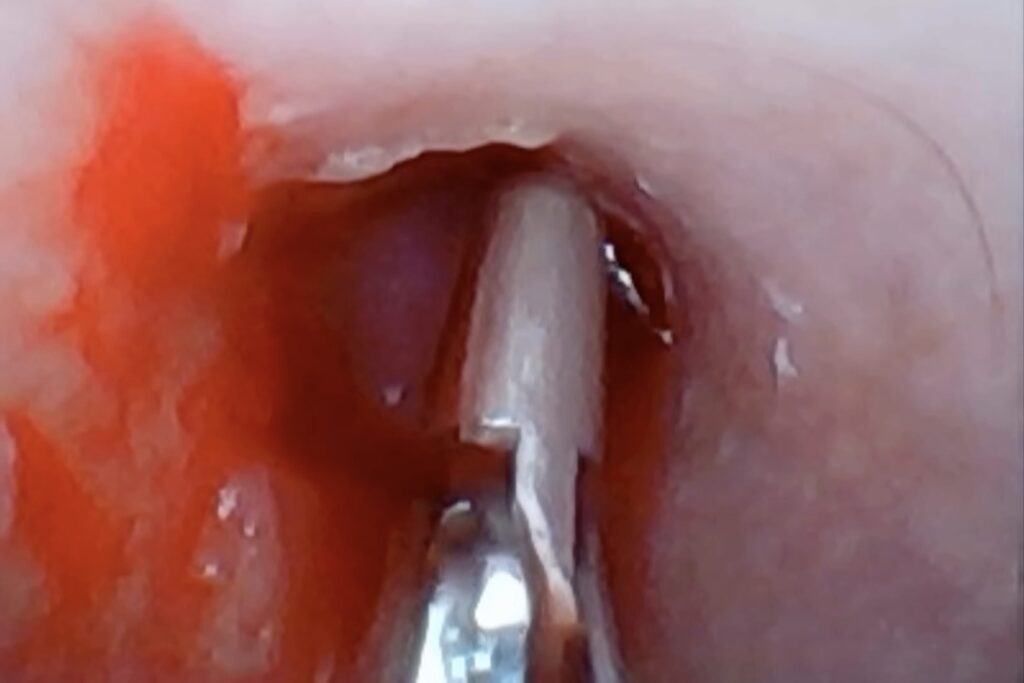

耳の奥にあるポリープが原因で、慢性外耳炎を引き起こしていた動物の例を紹介します。

症例

慢性外耳炎(耳漏が治らない)との主訴でご来院されました。

耳の奥をよく観察すると、ポリープができており、耳道を閉塞させていました。

治療

内科治療ではポリープがある限り、耳の閉塞・汚れは解除できないと判断し、外科手術でポリープを切除しました。

黄色矢印が耳の奥になったポリープです。

経過

病理検査:耳道ポリープ

術後経過は良好で、再発もなく過ごしています。耳が汚れることもなくなりました。